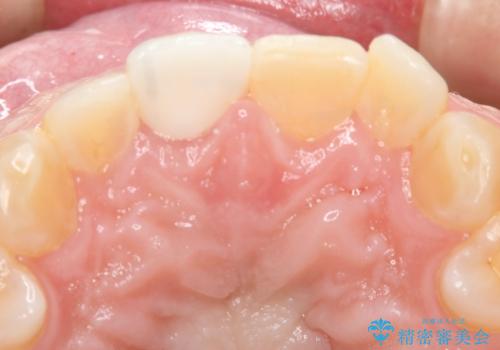

前歯が綺麗になったと大変満足して頂けました。